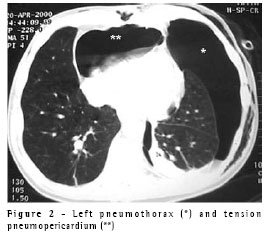

A 40-year-old male patient with atrial fibrillation was seen by a cardiologist. He was a nonsmoker and his chest X-rays showed hilar adenopathy in the right lower lobe. A computed tomography (CT) scan revealed a central mass invading the inferior pulmonary vein and compressing the left atrium (Figure 1A). An endobronchial lesion was seen in the right lower lobe bronchus, and a biopsy was performed. The results were consistent with neuroendocrine large cell carcinoma. The patient was submitted to three cycles of cisplatin-based chemotherapy and radiotherapy. Subsequent CT scans (Figure 1B) and bronchoscopic examinations revealed a highly positive response to the treatment. He was submitted to radical right pneumonectomy including a portion of the border of the left atrium (first resection margin positive at the level of the inferior pulmonary vein) and the perihilar pericardium. The pericardial defect was grafted with bovine pericardium and a 2-cm orifice was left in the suture line to allow fluid or air to freely exit the pericardial sac. The patient was discharged on the fifth postoperative day after a short and uneventful postoperative period. Ten days later, he returned to the hospital presenting postural hypotension and constant substernal pain. A chest X-ray showed pneumopericardium (Figure 1C) confirmed on a CT scan, which also revealed multiple air pockets and an air-fluid level in the pleural space, suggesting a bronchopleural fistula (Figure 1D). He was admitted to the hospital, a (36FR) chest tube was inserted into the right pleural space, and a bronchoscopy showed a tiny (1.0-mm) bronchial stump fistula. There were no signs or symptoms of infection, and the pleural fluid was clear, with fewer than 300 cells, 80% of which were eosinophils. The patient did not present intraoperative or postoperative air leakage through the chest tube. Antibiotics were given, and the evolution was excellent. The chest tube was withdrawn on the tenth postoperative day. The symptomatic pneumopericardium disappeared immediately after tube thoracostomy, and no empyema or other complications developed.